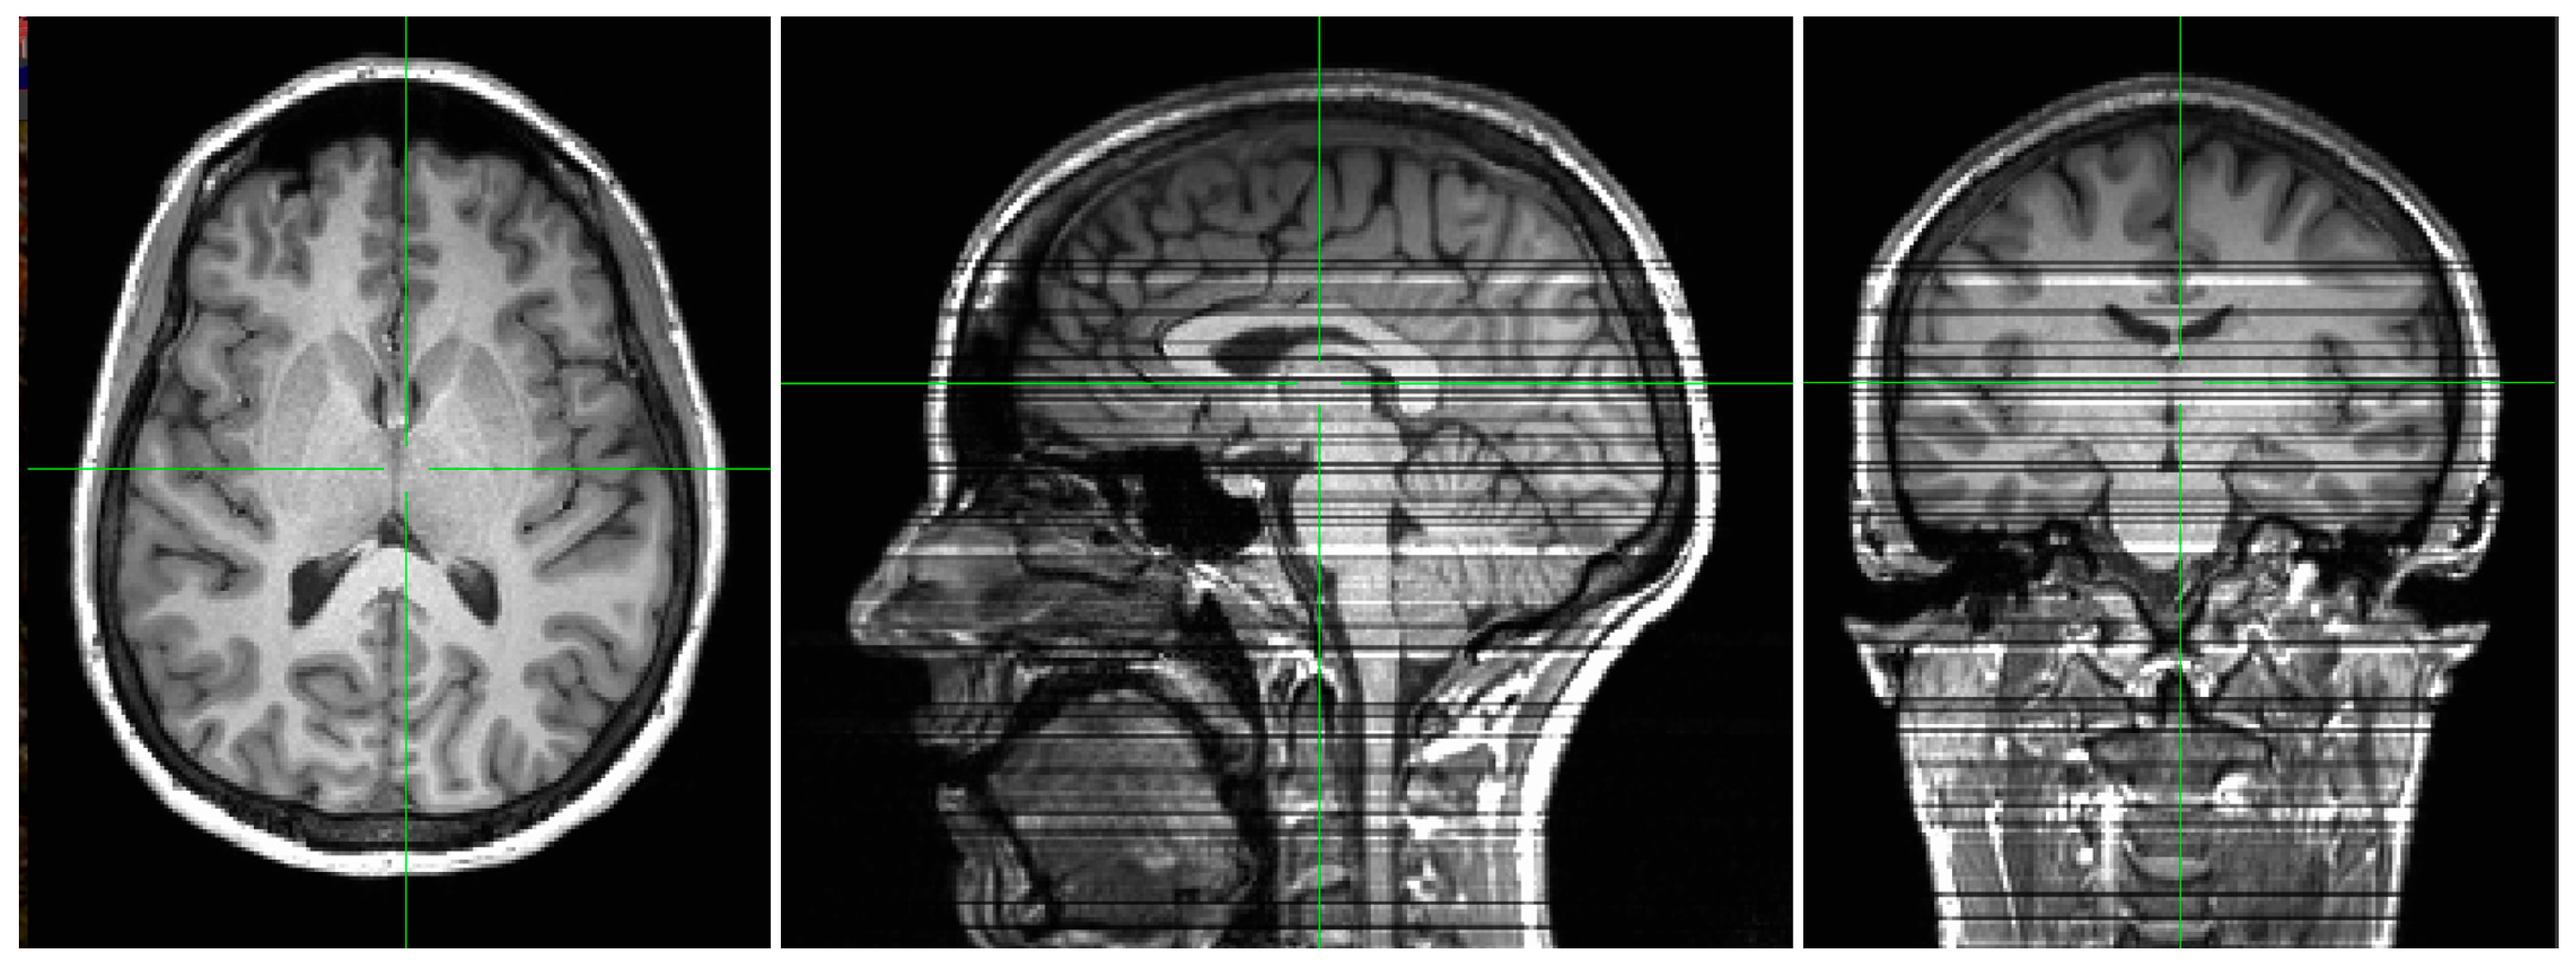

3.8. Cross-Field Adaptation and Evaluation Procedure

4.3. Cross-Field Validation Using Paired 3T/7T Datasets